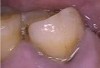

N.P.’s occlusal surfaces exhibited generalized extreme wear and/or erosion, and he complained of dentin hypersensitivity (Figure 2 and Figure 3). A caries risk assessment and diet recall was performed to assess the patient’s diet to determine its impact on the dentin hypersensitivity and caries risk. During the dietary assessment, N.P. reported severe GER problems limited his food selection.

Figure 2  Maxillary Arch

Figure 2